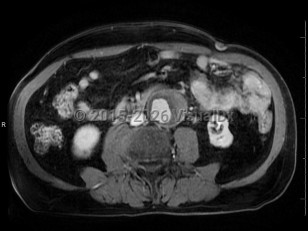

Metastatic pancreatic carcinomaMetastatic pancreatic carcinoma

Pyelonephritis

Hydronephrosis

Polycystic kidney diseasePolycystic kidney disease

Abdominal aortic aneurysmAbdominal aortic aneurysm

Aortic dissectionAortic dissection